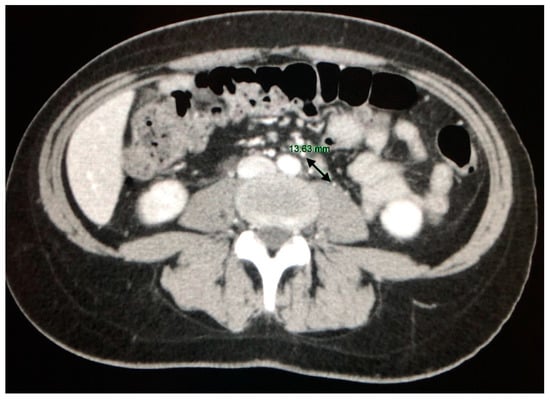

4. CT Features of Abdominal Sarcoidosis

4.1. The Involvement of Liver, Spleen and Abdominal Lymph Nodes